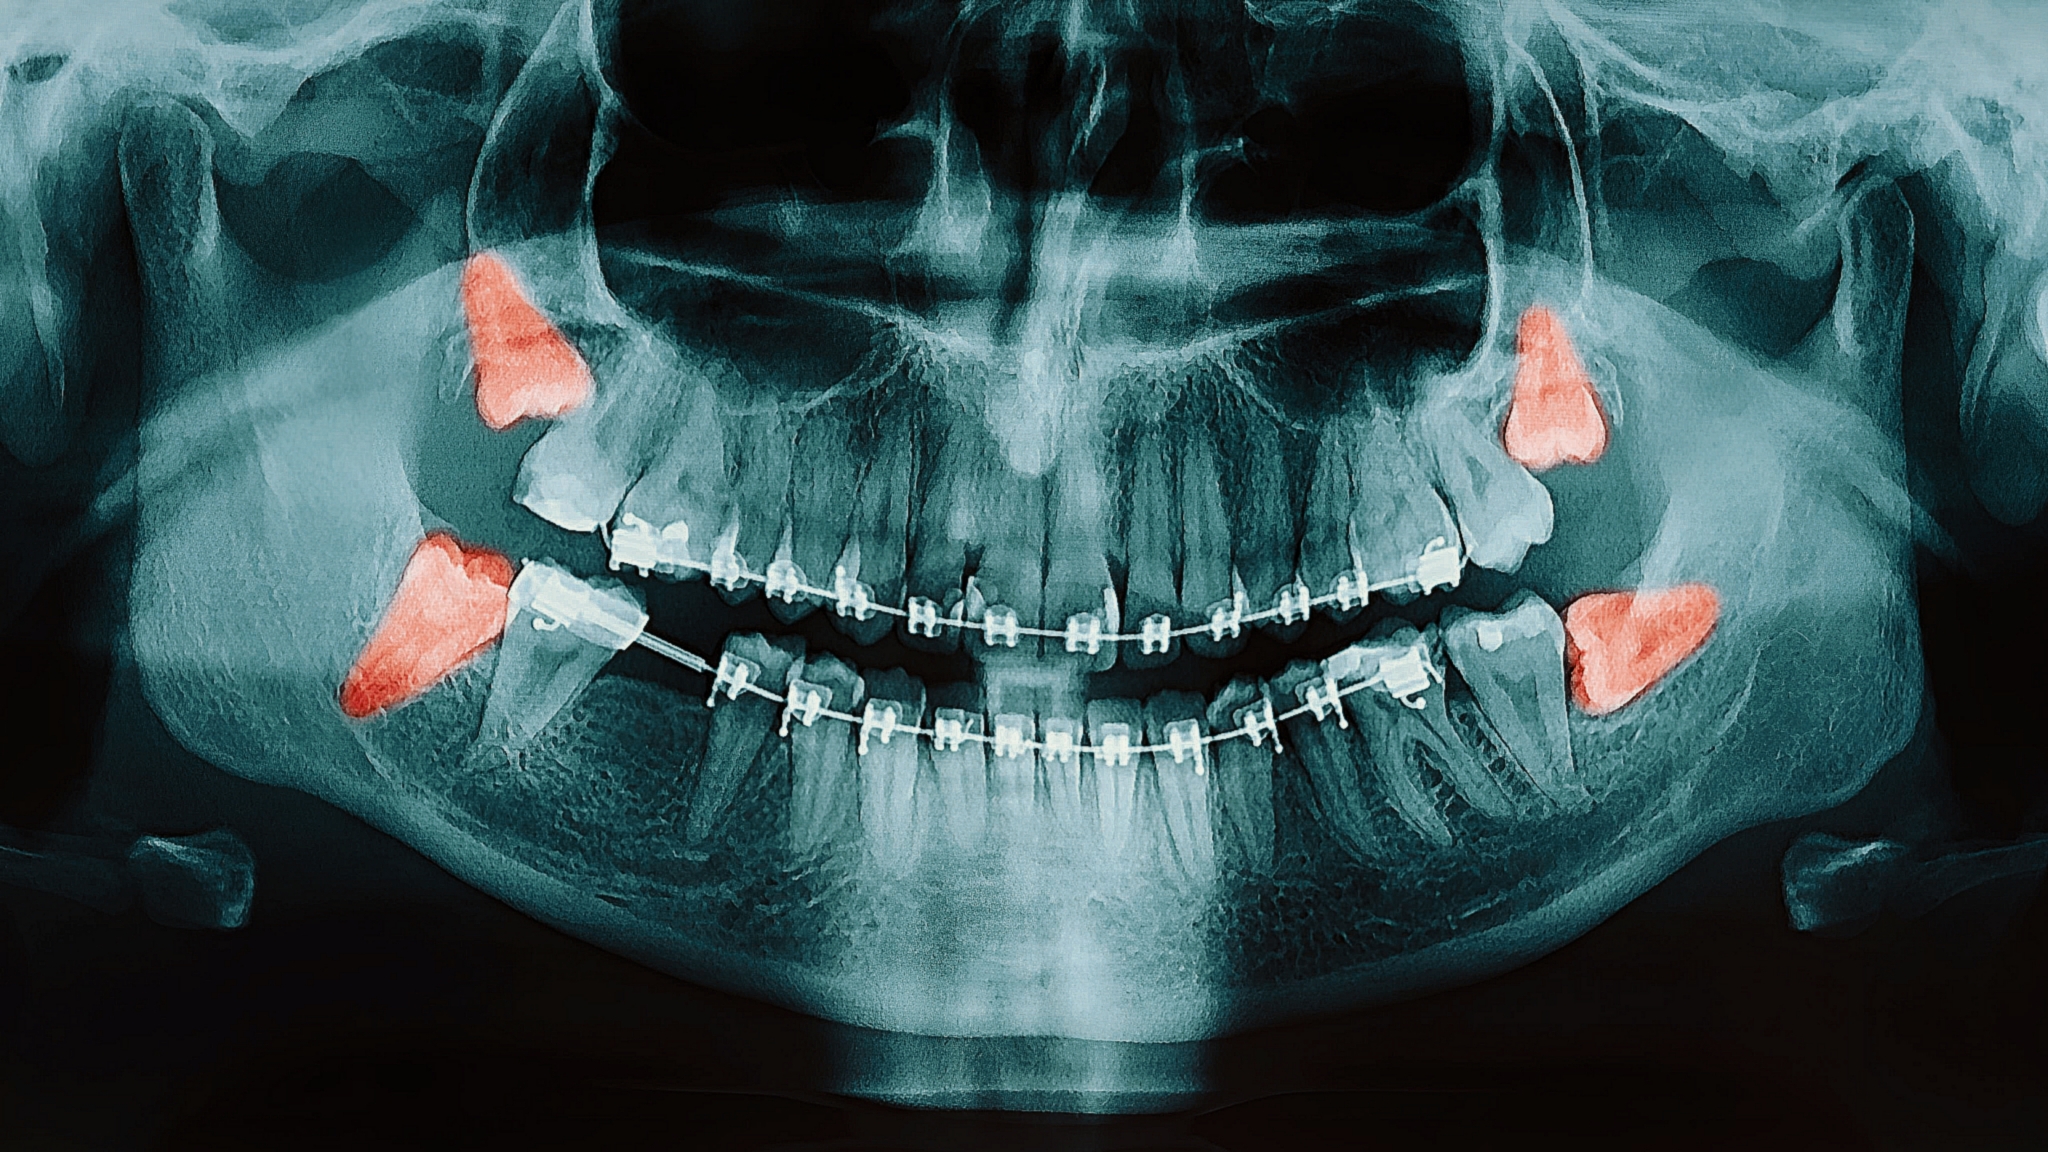

شاید برای شما هم پیش آمده باشد که دندانهای عقلتان کامل بیرون نیامده باشد یا حتی در قسمتی از فکتان نهفته باشد و فقط با گرفتن عکس رادیولوژی متوجه حضور آنها شده باشید.

برخی مواقع که دندان عقل به صورت ناقص رشد میکند و گاهی نیز شکل طبیعی ندارد و محل آن نیز مساعد نیست در این صورت دندان عقل میتواند مشکلاتی ایجاد کند که باید کشیده و یا جراحی دندان عقل انجام شود، ولی در حالتی که وضعیت دندان عقل نرمال باشد و جایگاه آن نیز مشکلی نداشته باشد، نیازی به کشیدن ندارد. دندان عقل در عمیقترین جای دهان بوده و دسترسی به آن سخت است. به همین دلیل تمیز نگه داشتن آن مشکل بوده و پوسیدگی در آن زیاد مشاهده میشود. دندان نهفته دندانی است که به علت ممانعت دندانهای مجاور، تنگی فک و کمبود فضای لازم تراکم و سفتی بیش از حد استخوان در زمان معین و خاص خود رویش نیافته.

خارج نمودن دندان عقل نهفته میتواند با موفقیت بالایی برای بیماران در سنین پائینتر (بین ۱۹-۳۰) انجام شود. با این حال زمانیکه دندانپزشک به شما میگوید که باید دندان عقلتان را بکشید، علتش این است که این دندان نهفته یا نیمه نهفته ممکن است به هزار و یک دلیل مشکلساز شود و نباید در دهانتان باقی بماند. دندانهای عقل پس از پوسیدگی موجب پوسیدگی دندانهای مجاور و آسیایی شما شده و عفونت در اطراف آن شکل میگیرد و گاهاً در صورت پیشرفت ضایعه و عفونت ممکن است با بستری شدن در بیمارستان نیز همراه شود. دندان عقل به علت سخت بودن انجام اقدامات بهداشتی بار میکروبی دهان را بالا میبرد.

اگر دندان عقل جای کافی برای رشد نداشته باشد یعنی نهفته یا نیمه نهفته باشد باید با جراحی این دندان را خارج کرد.

ریشههای دندان عقل بطوری نامشخص و کج و گاهاً با قوسهای زیادی هستند و به همین دلیل اگر دندان مقابل و جونده در فک مقابل خود نداشته باشند و در جویدن شما تأثیرگذار نباشند، از آنجا که برای ترمیم و پر کردن و روت کانال کردن و پوسیدگی عمیق ریشه در اغلب موارد غیرممکن است بنابراین اگر دندان عقل را از دهانتان خارج کنند تمام مشکلات احتمالی برطرف میشود.

زمانی که دندان عقل نیمه نهفته باشد بخشی از تاج مشخص است و لثه روی دندان را گرفته و در این صورت اگر بین لثه و تاج دندان مواد غذایی بماند اغلب عفونتهای شدیدی میکند.بطور معمول دندان عقل پس از ۲۰ سالگی امکان رویش و تکامل کمتری دارد، بنابراین توجه کنید که اگر تا این سن رویش پیدا نکرده است باید به فکر جراحی این دندان باشید.